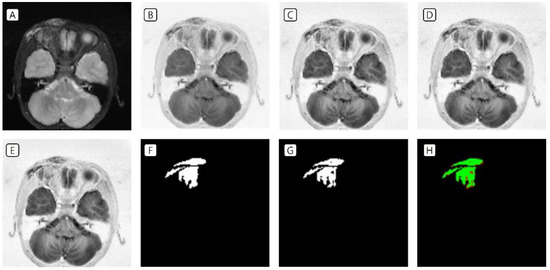

3.1. Cases: Data of the Training Set

3.2. Cases: Data of the Test Set